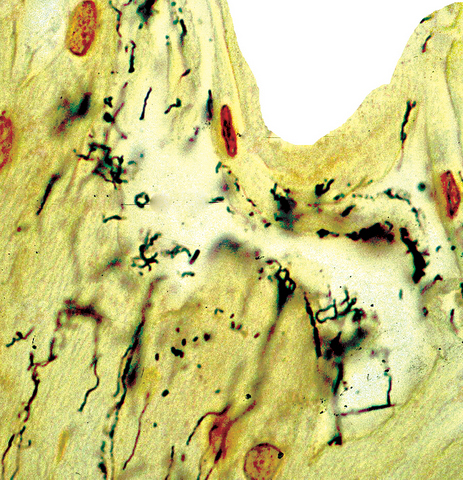

- Lymph node:

- Primary syphilis:

- Capsular and pericapsular fibrosis, follicular hyperplasia, diffuse interfollicular plasma cells, prominent endarteritis outside the capsule

- Noncaseating granulomas and abscesses are rare

- Spirochetes easiest to identify within blood vessel walls

Microscopic (histologic) images

Contributed by Silvija P. Gottesman, M.D., Hillary Rose Elwood, M.D., Mark R. Wick, M.D. and AFIP images

- Silver stains: Warthin-Starry or Steiner stain (41% sensitive) (J Cutan Pathol 2004;31:595)